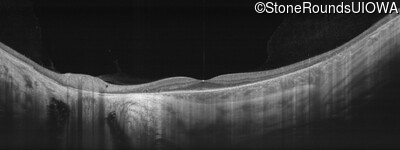

Age at visit: 30 years

This 30 year old man has had some difficulty seeing in dim light for the past few years.